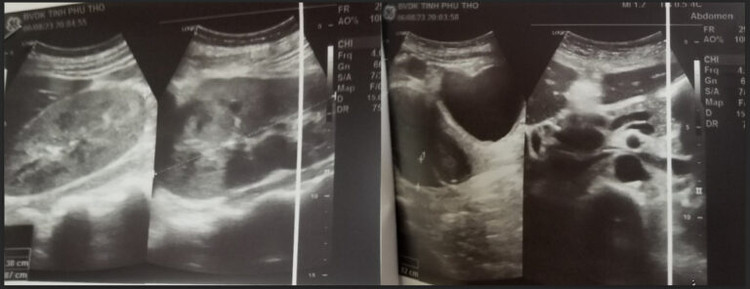

Hình ảnh siêu âm ruột thừa và thận của bệnh nhân trước và sau khi điều trịHình ảnh siêu âm ruột thừa và thận của bệnh nhân trước và sau khi điều trị

Khi thăm khám, người bệnh sốt 38oc, không khó thở, không phù; da, niêm mạc hồng; đau bụng quanh rốn và hố chậu phải, có phản ứng thành bụng; Tim nhịp đều, phổi không ran, bụng mềm. Kết quả siêu âm ổ bụng cho thấy hình ảnh viêm ruột thừa và hai thận có hình ảnh bệnh thận mạn tính.

Người bệnh được chỉ định phẫu thuật cắt ruột thừa viêm, điều trị theo phác đồ bao gồm: truyền dịch, kháng sinh, điều chỉnh rối loạn nước điện giải, áp dụng chế độ ăn giảm đạm và bổ sung ketoamin kết hợp lọc máu cấp cứu. Rất may mắn, chức năng thận cải thiện tốt sau điều trị.